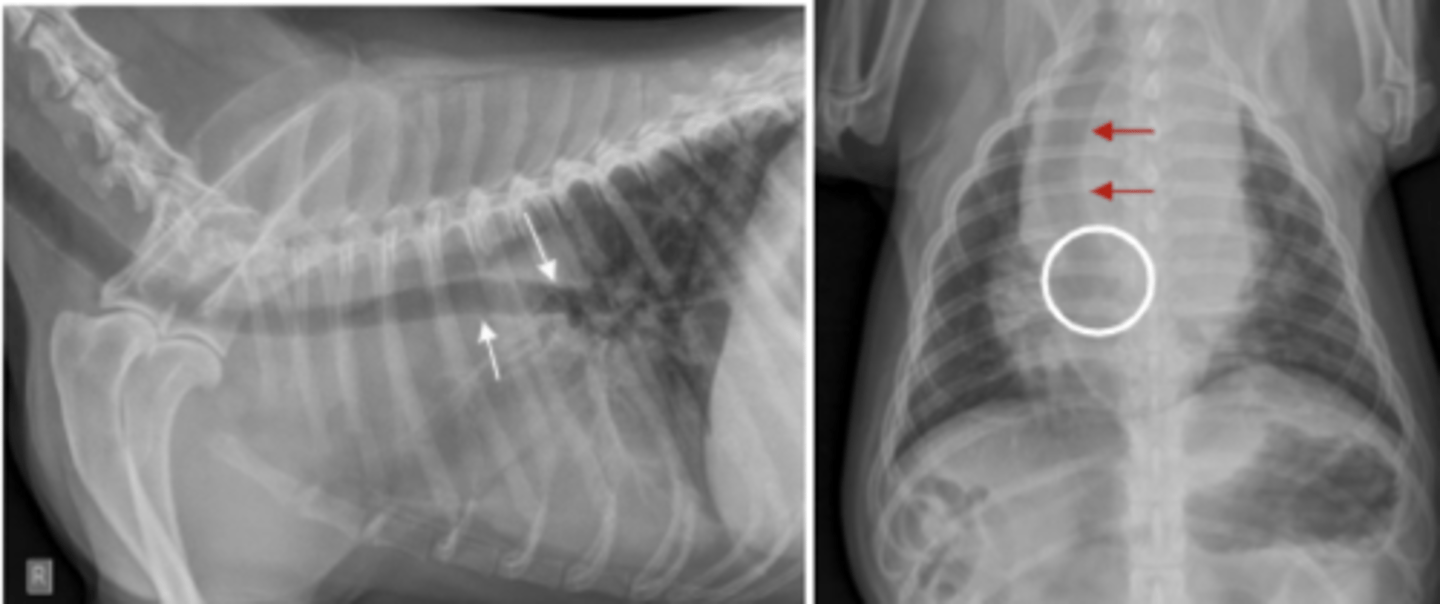

aumento del aurículo izquierdo

patología: